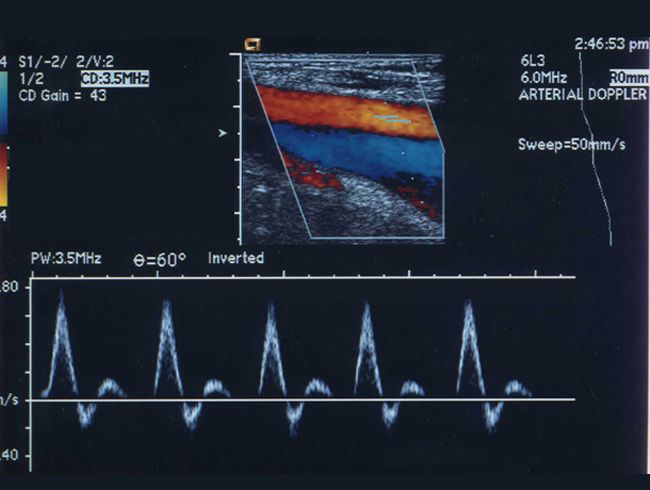

Nature of vascular abnormality? Options to investigate?

- Is the primary abnormality in extracranial arteries or intracranial arteries?

- Doppler US is the least expensive study to evaluate carotid bifurcations. MR angiogram and CT angiogram are non-invasive studies to investigate extra and intracranial arteries. Digital subtraction intra-arterial contrast angiogram (DSA) is invasive and definitive. If interventional therapy is contemplated, such as retrieval of clot from major arteries one needs to do dedicated invasive digital subtraction contrast angiogram.

|

US of carotids

No radiation |